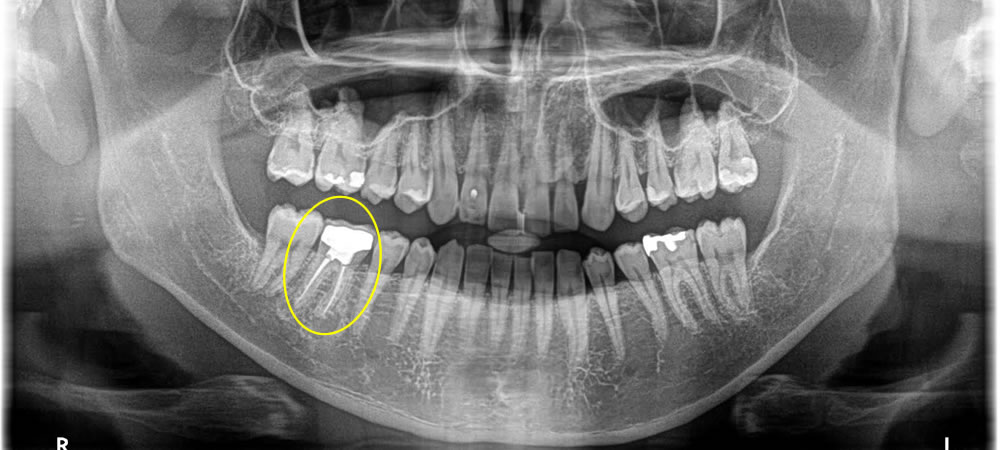

歯根先端に膿が溜まった歯を抜歯してインプラントで治療した症例

▼根の先端に膿が溜まり、痛みを感じる歯を抜歯してインプラントで治療した症例をご紹介します。

こちらの患者さまは、根の先端に膿が溜まり、腫れて痛いとの事で来院されました。治療方法を話し合った結果、インプラントでの治療をご希望されました。

まずは当該歯を抜き、中の膿が溜まっている所をキレイに掻爬し、人工の根を入れて骨を作るところまでを1回の処置で行いました。これを1回で行う事により、2回に分けてやるよりも骨の減りを最小限に抑える事ができ、治療期間を短くする事ができます。